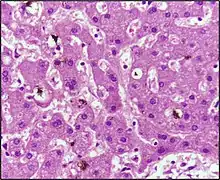

Hepatic pathophysiology

Hepatic jaundice (hepatocellular jaundice) is due to significant disruption of liver function, leading to hepatic cell death and necrosis and impaired bilirubin transport across hepatocytes. Bilirubin transport across hepatocytes may be impaired at any point between hepatocellular uptake of unconjugated bilirubin and hepatocellular transport of conjugated bilirubin into the gallbladder. In addition, subsequent cellular edema due to inflammation causes mechanical obstruction of the intrahepatic biliary tract. Most commonly, interferences in all three major steps of bilirubin metabolism — uptake, conjugation, and excretion — usually occur in hepatocellular jaundice. Thus, an abnormal rise in both unconjugated and conjugated bilirubin (formerly called cholemia) will be present. Because excretion (the rate-limiting step) is usually impaired to the greatest extent, conjugated hyperbilirubinemia predominates.[34]

The unconjugated bilirubin still enters the liver cells and becomes conjugated in the usual way. This conjugated bilirubin is then returned to the blood, probably by rupture of the congested bile canaliculi and direct emptying of the bile into the lymph exiting the liver. Thus, most of the bilirubin in the plasma becomes the conjugated type rather than the unconjugated type, and this conjugated bilirubin, which did not go to the intestine to become urobilinogen, gives the urine a dark color.[35]